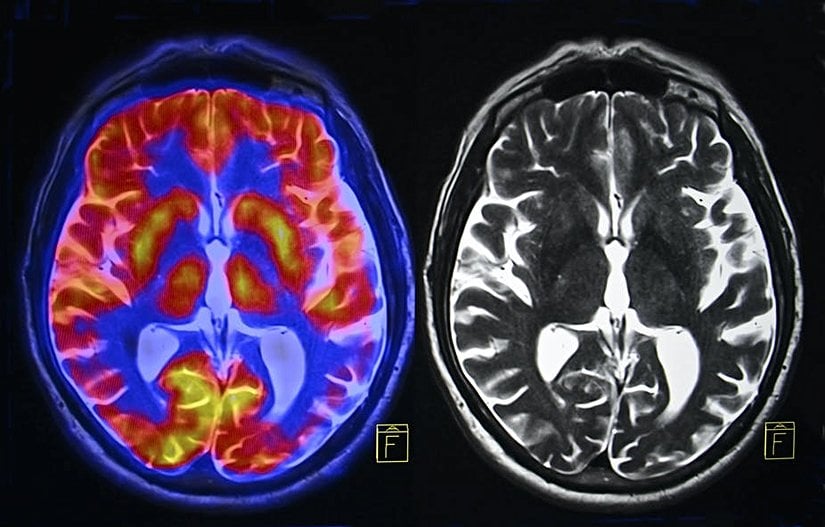

Tekrarlanan stres, vücutta oluşan kalıcı iltihaplanmanın en önemli tetikleyicilerinden biridir. Kronik iltihaplanma da diyabet ve kalp hastalığı gibi birçok sağlık sorununa yol açabilir. Beyin normalde, dolaşımdaki moleküllerden bir kan-beyin bariyeri ile korunur. Ancak tekrarlanan stres halinde, bu bariyer sızdırır hale gelir ve dolaşımdaki enflamatuar (iltihaba neden olan) proteinler beyne girebilir.

Beyindeki hipokampus bölgesi, öğrenme ve hafıza kullanımında kritik bir bölgedir ve özellikle bu tür tehlikelere karşı oldukça savunmasızdır. Araştırmalar, iltihaplanmanın motivasyona ve zihinsel çevikliğe bağlı beyin sistemlerini olumsuz yönde etkileyebileceğini göstermiştir.

Kronik stresin; kortizol ve kortikotropin salgılatıcı faktör (KSF ya da CRF) de dahil olmak üzere beyindeki çeşitli hormonlar üzerinde de etkisi vardır. Yüksek ve uzun süreli kortizol seviyesi hipokampusun büzülmesinin yanı sıra duygudurum bozukluklarına yol açar. Ayrıca düzensiz adet döngüsü gibi birçok fiziksel soruna da neden olur.